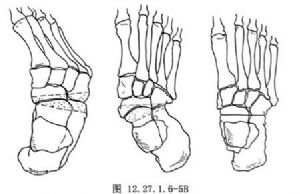

用大切骨刀切除跟骨和距骨关节面,根据畸形的性质与程度,切除适量的楔形骨质。如为内翻畸形,应切除以外侧为基底的楔形骨质;反之如为外翻畸形,则应切除以内侧为基底的楔形骨质(图12.27.1.6-5A)。用切骨刀横行切除跟骰关节面,如有足前部内收,应切除以外侧为基底的楔形骨质;如为外展畸形,则应切除以内侧为基底的楔形骨质(图12.27.1.6-5B)。切除距舟关节面,如有高足弓,应切除以背侧为基底的楔形骨质。如显露困难,宜在内侧做一纵行辅助切口。切骨后观察足部畸形矫正情况,适当修整骨面,使三处骨面有良好接触,以便完全矫正畸形,并有利于骨愈合(图12.27.1.6-5C)。保留取下的骨质,去除软骨部分,作为松质骨植骨,植于各关节周围,要特别注意在距舟关节部位多植些碎骨,防止形成假关节。